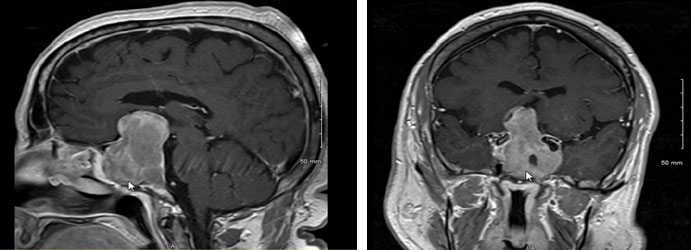

就其形態(tài)而言,垂體腫瘤分為微腺瘤(直徑小于10毫米,通常為封閉型,侵襲性較低)和大腺瘤(封閉于鞍區(qū)邊界,擴(kuò)張型或侵襲性。微腺瘤通常是由臨床表現(xiàn)或激素分泌過多的結(jié)果診斷的,或者,當(dāng)出現(xiàn)神經(jīng)營養(yǎng)不良時,由為另一種適應(yīng)癥(如頭部外傷)進(jìn)行的成像的偶然發(fā)現(xiàn)或尸檢發(fā)現(xiàn)診斷的。大腺瘤通過激素分泌過多和分泌不足(如果存在)或通過神經(jīng)眼科和神經(jīng)系統(tǒng)表現(xiàn)來診斷。也可以順帶找到。一雖然沒有組織學(xué)差異,但侵襲性腫瘤生長更快,導(dǎo)致鞍區(qū)侵蝕和鄰近結(jié)構(gòu)的浸潤,如硬腦膜、骨、蝶竇和海綿竇。垂體腫瘤的形態(tài)通過影像學(xué)評估,并通過手術(shù)和病理證實。有時很難評估腫瘤的侵襲程度,因為垂體腺瘤不呈現(xiàn)的包膜,只是由垂體細(xì)胞和網(wǎng)狀蛋白網(wǎng)絡(luò)形成的“假包膜”。因此,盡管侵襲性與大腺瘤更相關(guān),但它也可以存在于微腺瘤中。